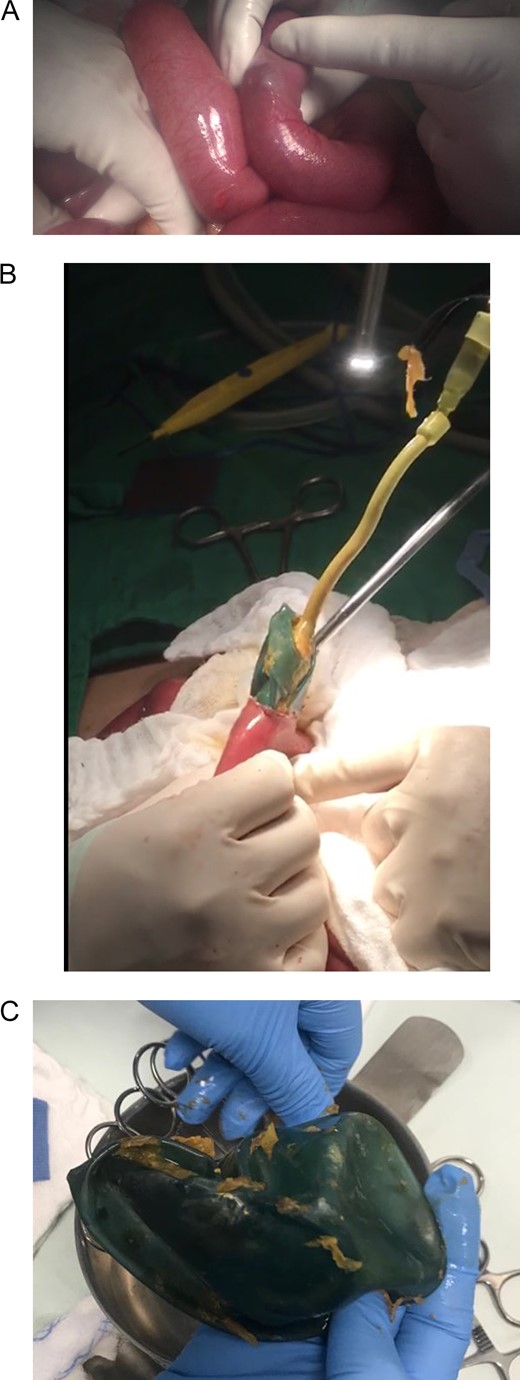

Bowel obstruction due to the migration of the deflated intragastric balloon was suspected. Following a laparoscopic approach, the intestinal loops were dilated, and 100 ml of inflammatory fluid were noticed in the abdominal cavity. However, the definite site of obstruction could not be accessed (Fig. 2). Due to this, a laparotomy was decided. There was an important dilatation of all the loops of the small bowel, and the bowel walls were thickened but no perforation was detected. Near the ileocecal valve, a clear bulging of the bowel wall caused by the deflated impacted balloon was externally visible. A 3 cm transverse enterotomy was performed and the deflated gastric balloon was gently pulled out. The enterotomy was subsequently closed and the rest of the procedure was completed without complications (Fig. 3).

(A) Laparotomy, showing gastric balloon within the bowel. (B) Removal of the deflated gastric balloon. (C) Deflated gastric balloon.

The gastric balloon was completely deflated with a small tear in its wall, but the mechanism of rupture of the balloon is not known. However, it is clear that after the balloon deflated, and intestinal migration and subsequent obstruction occurred. The postoperative course of this patient was uneventful, the nasogastric tube was removed at the second postoperative day, and after observing good oral tolerance to sips of liquids, a full diet was started. She completed a 7-day antibiotic course and was discharged without complications. On follow-up controls, the patient shows signs of recovery.